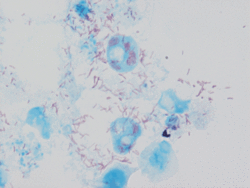

| Rickettsia conorii observed in Vero cells (red rods; magnification ×1,000).[1] | |